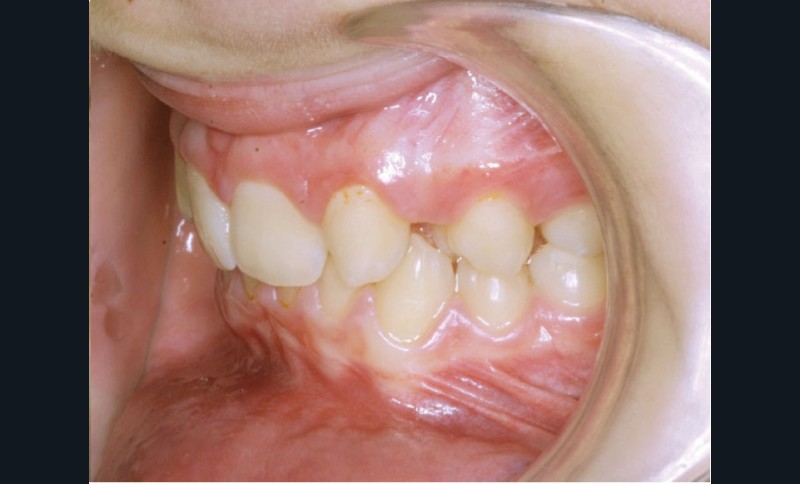

Ludivine T. âgée de 12 ans et demi présente une agénésie des deux incisives latérales maxillaires dans un contexte occlusal de classe II division 2 (fig. 1 à 3).

Les vues endo-buccales (fig. 2) montrent la classe II division 2 occlusale associée à une forte supraclusion incisive et l’évolution spontanée de 13 et 23 pratiquement en place de 12 et 22. Il persiste cependant un diastème disgracieux entre 13 et 11.

Le contexte de classe II occlusale, l’évolution spontanée mésiale des 13 et 23 et le diamètre mésio-distal favorable des canines conduisent au choix d’une thérapeutique par fermeture orthodontique des espaces d’agénésie avec substitution de 13 et 23 en place de 12 et 22. Le traitement de l’arcade mandibulaire ne nécessitant pas d’extraction, l’occlusion de fin de traitement sera donc une classe II molaire thérapeutique.